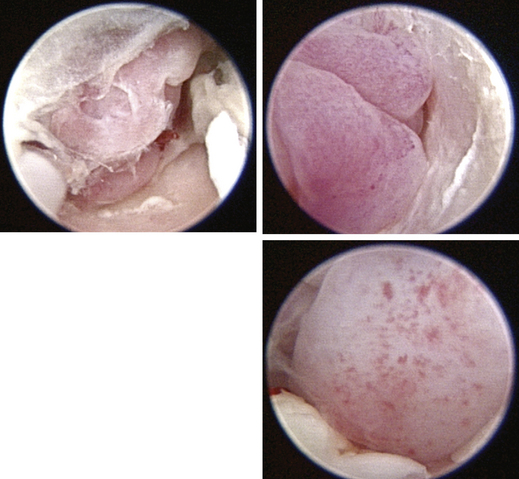

image

Figure 20-11 Bulging pars tensa in a dog with otitis media.

Figure 20-12 Scaly pars tensa in a dog with otitis media.

Figure 20-13 Normal feline tympanic membrane. 1, Pars flaccida; 2, pars tensa; 3, stria mallearis; C, caudal; D, dorsal; R, rostral; V, ventral.